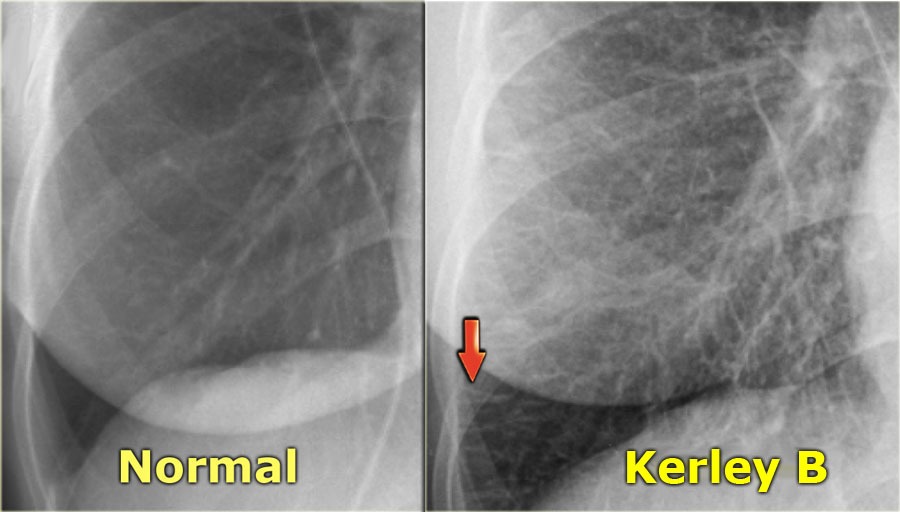

Kerley B lines

Thin linear opacities seen on chest X-ray indicative of interstitial edema.

CHF Interstitial Findings

Four Key Findings in Pulmonary Interstitial Edema:

Thickening of the interlobular septa—Kerley B lines—and fluid in the central connective tissue of the lungs—Kerley A lines